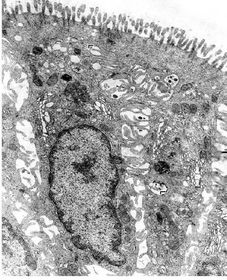

TEM of enterocytes covering the villi

Apical surface of enterocytes TEM A : Microvilli B : Zonula occludens C : Zonula adherens D : Desmosome